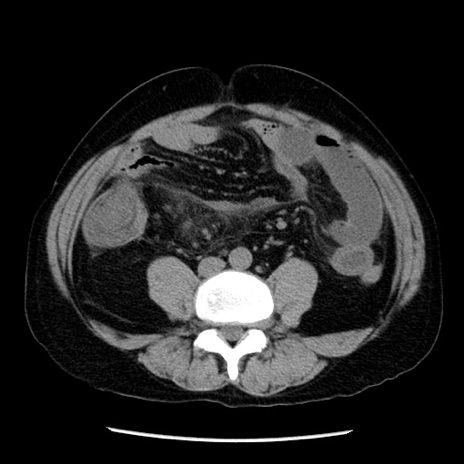

冠状断像

【症例】40歳代男性

【現病歴】2日前から胃痛あり。徐々に周期的な激痛に変化した。本日になっても激痛があるため受診。

【身体所見】意識清明、BT 38-39℃台あり、腹部:膨満、やや硬、右下腹部に圧痛あり。

【データ】WBC 8500、CRP 23.26